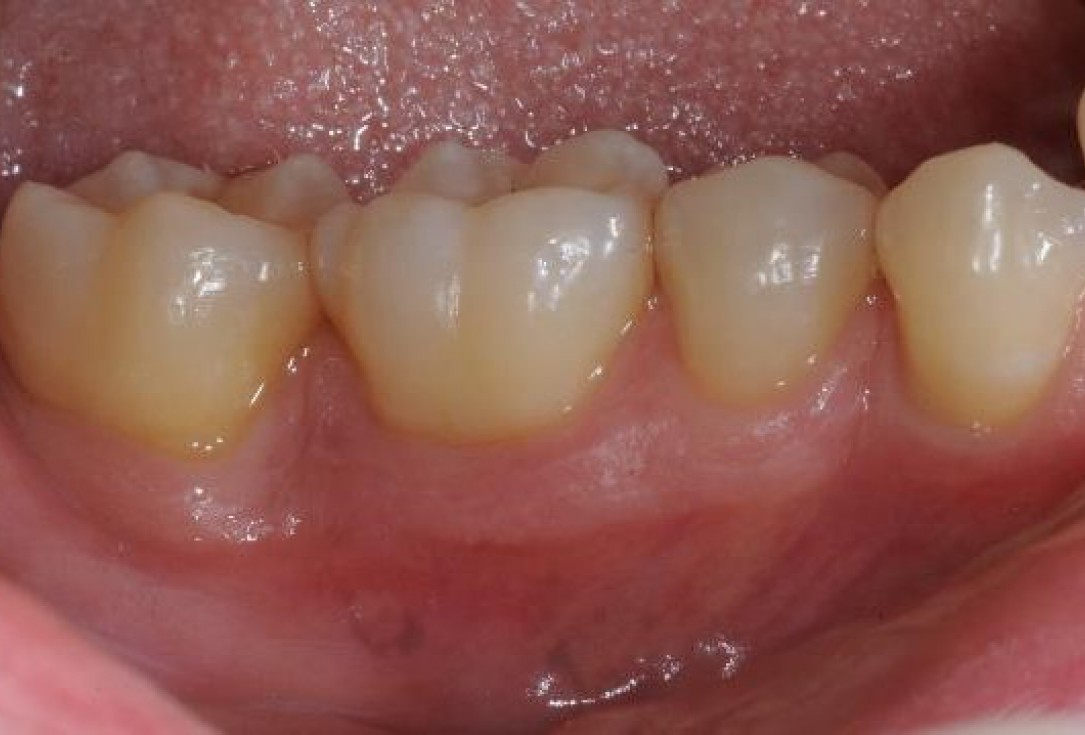

15/22 - Clinical situation 12 months post-operative. Buccal view.

Deep intrabony defects treated using Straumann® Emdogain® - Dr. M. Stefanini